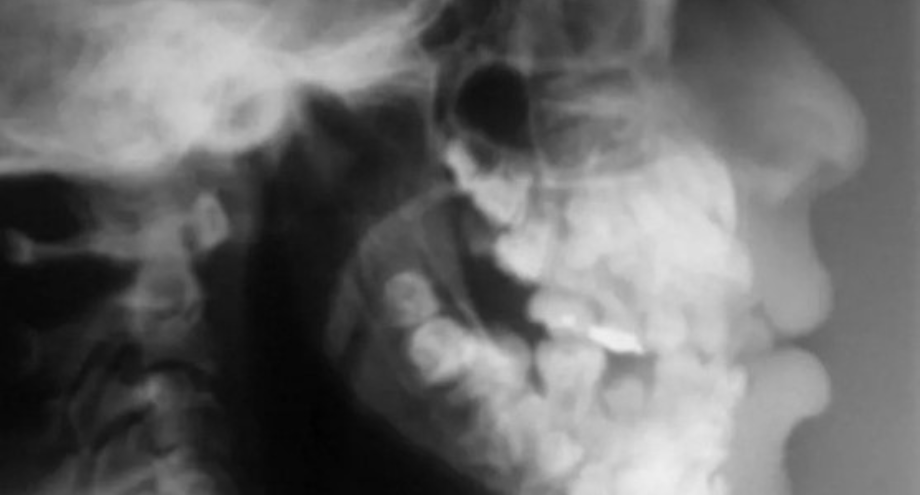

Las consecuencias de la respiración bucal crónica en la salud oral